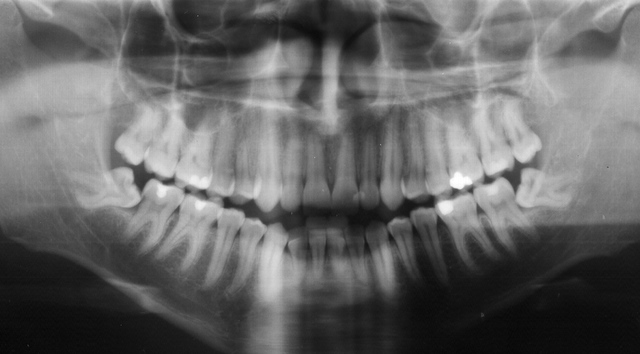

A sua extração está indicada na ausência de espaço para a erupção, no posicionamento horizontal do siso, nos quadros de dor e quando se inicia a erupção e esta não se completa, ou seja, há erupção parcial do siso. Quando se faz a extração de um dos sisos inferiores, também poderá ser indicada extração do superior (do mesmo lado) e vice-versa, pois a presença isolada de um deles pode provocar uma desarmonia na mordida.

Quando este se apresentar saudável, estando ele dentro do osso ou em posição correta na boca. O importante para manter este dente com saúde é visitar regularmente seu cirurgião dentista, para que este faça uma avaliação, e que o paciente faça uma boa higienização do dente!